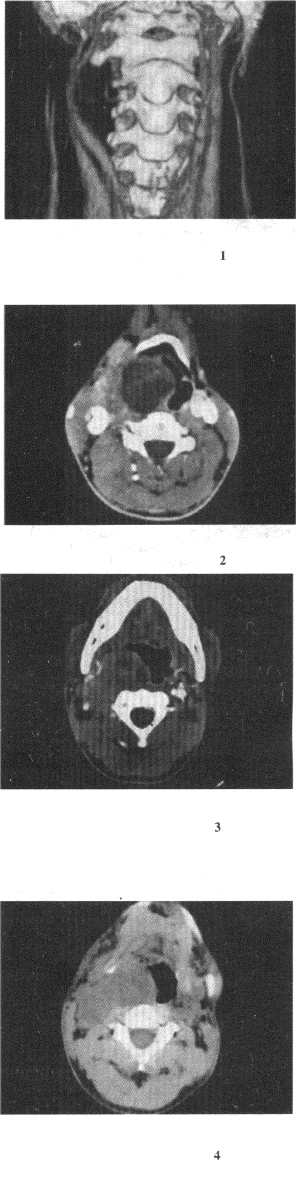

男,41岁,右侧咽部不适2年余,有异物感,声音嘶哑,CT如图,最可能的诊断是()